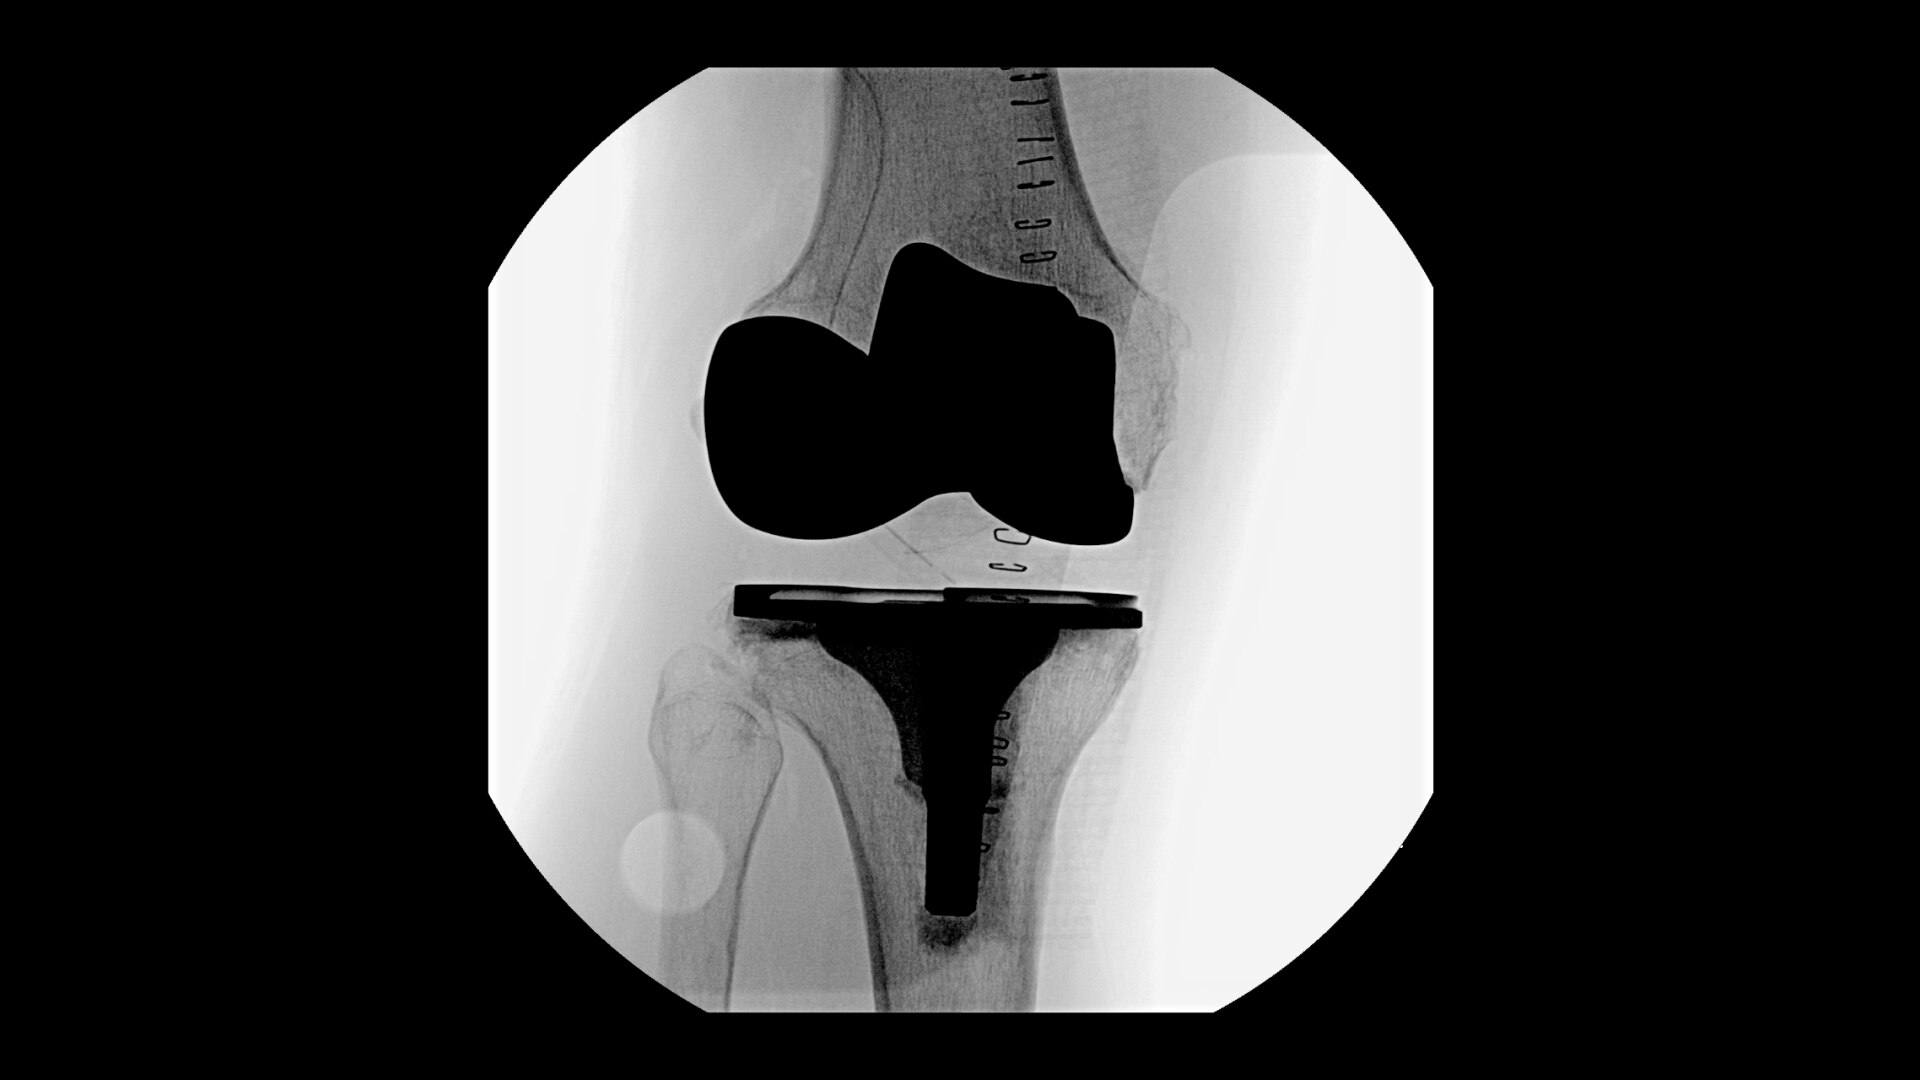

Complex orthopedic procedures require powerful imaging systems. OEC premium C-arms perform in a variety of procedures such as:

• Ankle arthrodesis procedures

• Distal radius fracture fixation

• Humeral fracture

• Hip fracture fixation

• Knee replacement

• Hip replacement

• Pilon fracture fixation

• Shoulder fracture reduction

OEC C-arms provide orthopedic imaging with a large field of view optimized to clearly visualize orthopedic anatomy, such as the entire long bone femur or minute fractures in extremities. A clear display with comfortable viewing can easily show AP and lateral views, enabling efficient procedure planning.